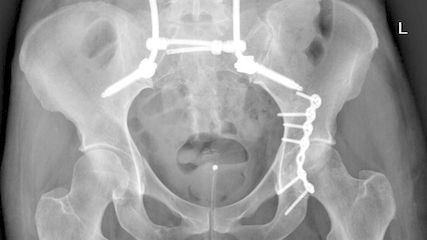

Der interdisziplinäre Ansatz ist entscheidend. Liegt beispielsweise eine instabile HWS-Verletzung mit Vertebralis-Dissektion vor, so ist die Wiederherstellung stabiler Verhältnisse für u.a. die A. vertebralis vordergründig (Abb.2–4). Dieser operative Eingriff erfolgt bereits unter therapeutischer Heparinisierung. Je nach Ausmaß der Gefäßverletzung wird dabei ein- oder zweizeitig die endovaskuläre/offene Therapie zur Gefäßreperfusion durchgeführt. Aktuelle interdisziplinäre Therapieempfehlungen:

Die Indikationsstellung und Wertigkeit der lumbopelvinen Stabilisierung

Die lumbopelvine Stabilisierung bietet als etabliertes Verfahren eine hohe biomechanische Stabilität. In diesem Artikel werden anhand der aktuellen Literatur und Empfehlungen die ...